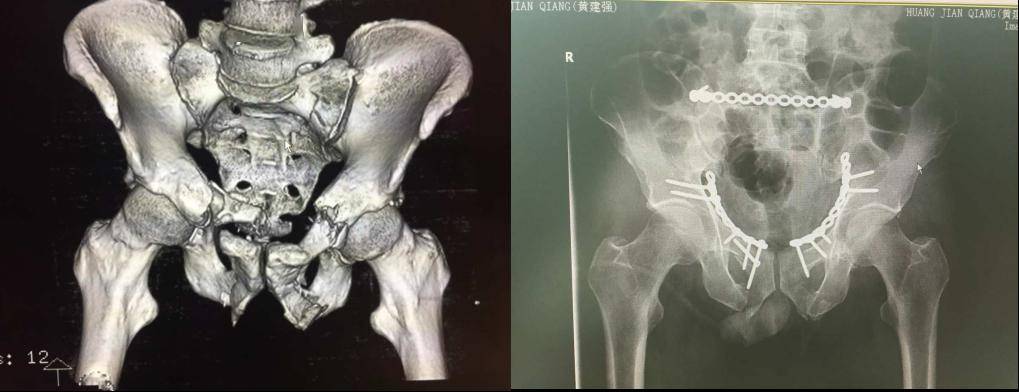

复杂骨盆骨折C型骨折、多发伤患者,膀胱破裂。失血性休克,情况凶险。通过一期损伤控制抢救生命,泌尿科膀胱修补造瘘,ICU监护生命支持,后期骨科前后路髋臼骨盆微创手术内固定等多学科救治,患者4周就可以恢复站立行走,体现了我院救治危急重症的综合能力。

装修工人高处坠落致复杂双柱髋臼骨盆骨折,手术较为复杂。科室通过前方腹直肌旁单一入路微创手术,就可以完成所有骨盆髋臼骨折的固定,骨盆正位显示术中良好的复位与固定。3年后患者恢复良好,仍能从事体力工作。